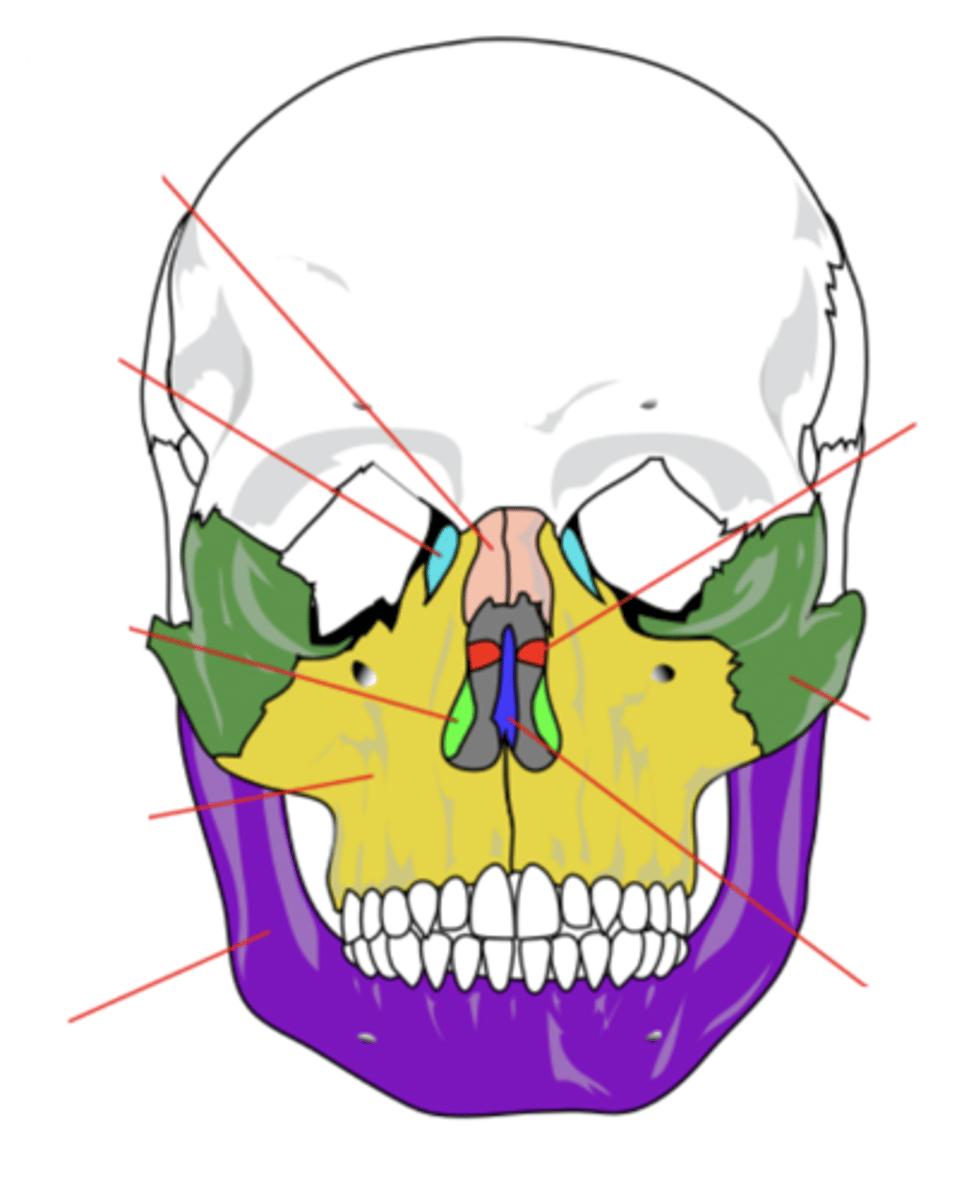

Facial Bones (14)

- Maxilla (2)

- Mandible

- Lacrimal (2)

- Palatine (2)

- Inferior conchae (2)

- Vomer

- Nasal (2)

- Zygomatic (2)

(Many Mammals Like Playing In Very Nice Zoos)

Maxilla Bone (2)

Upper jaw bone (yellow)

Mandible Bone

Lower jaw bone (purple)

Lacrimal Bone (2)

Small fragile bone making up part of the front inner walls of each eye socket and providing room for the passage of the lacrimal ducts (light blue)

Palatine Bone (2)

Bone that forms the hard palate and parts of the nose and orbits (red)

Inferior Conchae Bone (2)

The thin, scroll-like bones that form part of the interior of the nose (light green)

Vomer Bone

Bone that forms the inferior portion of the nasal septum (blue)

Nasal Bone (2)

Bone that forms the bridge of the nose (pink)

Zygomatic Bone (2)

Cheek bone (green)